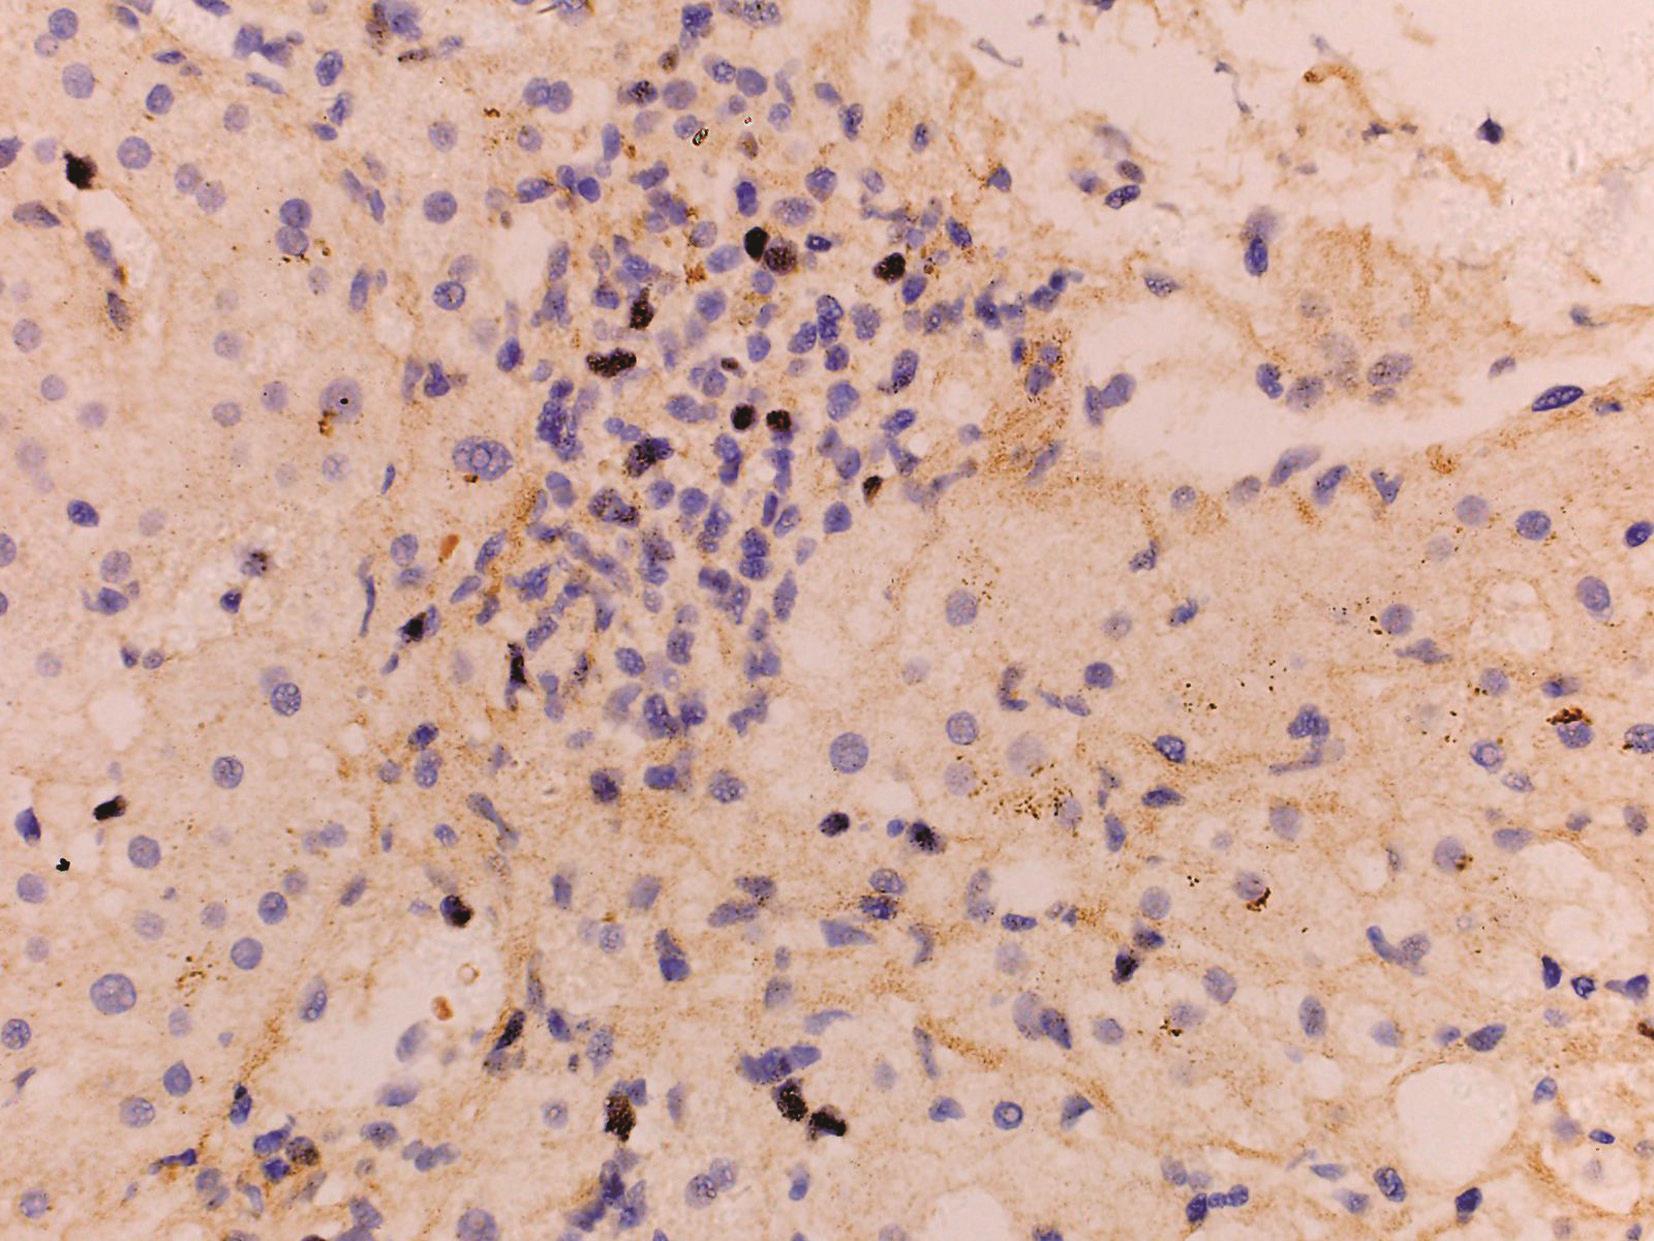

腺病毒肝炎常见于免疫缺陷的儿童或成人,如HIV患者,造血系统恶性肿瘤或移植后患者。病理改变主要表现为广泛的肝细胞坏死和轻微的炎症反应,肝细胞内易查见病毒包涵体(图4-18-3)。病毒包涵体位于肝细胞核内,圆形、嗜碱性、淡染。此型病毒常引起严重的肝炎,并导致肝衰竭,预后差。腺病毒免疫组化染色(图4-18-4)和外周血病毒DNA定量可证实病毒感染。

图4-18-4 肝组织腺病毒免疫组化染色